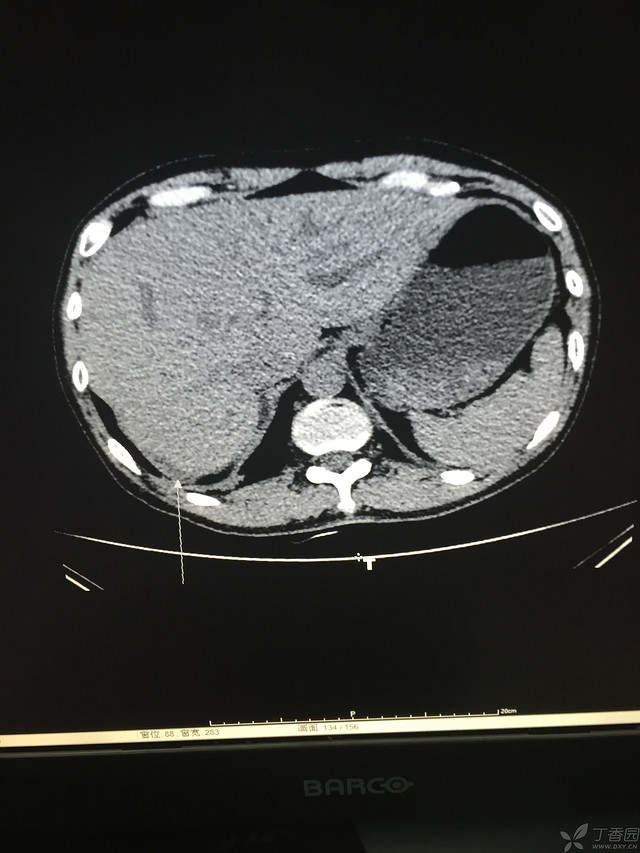

胸痛三天,加重三小时(CT是心包高密度影是什么)

患者性别:男

患者年龄:64岁

简要病史:三天前休息时突发胸前区疼痛伴大汗,到当地医院输液治疗后缓解,3小时前情绪激动后再次出现胸痛伴大汗,胸部压迫感,持续不缓解入院,到当地医院测血压180/?mmHg泵入硝酸甘油转入我院。

体格检查:血压94/72mmHg(右侧)96/74mmHg(左侧),心率78此/分,其他未见阳性体征

临床诊断:

治疗经过: